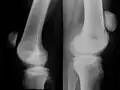

Zuggurtungsosteosynthese

Das Grundprinzip der Osteosynthese an der Kniescheibe wird mit der Zuggurtung am besten erreicht. Dieses Verfahren wurde in den 1960er Jahren aus Drahtnahtverfahren unter dem ingenieurtechnischen Aspekt von Spannbeton entwickelt: Hier dienen Stahlstäbe der Zugstabilität, während der Beton die Druckstabilität sicherstellt. Der eingerichtete Knochen der Kniescheibe ist druckstabil, während eine Drahtschlinge, die auf der Vorderfläche des Knies an der Basis (Quadriceps-Sehne) und der Spitze (Patellar-Sehne) gelegt ist, die Zugstabilität erzeugt. Die Drahtschlinge wird vorteilhaft als O-Schlinge geführt, wodurch eine Strangulierung der Sehnenansätze vermieden wird. Andere Operateure führen die Schlinge in Form einer 8, was aber bei Spannungserhöhung des Drahtes zu einer Einengung der Sehnenansätze führt. Der Vorteil der Zuggurtung besteht darin, dass die Stabilität in Bewegung des Kniegelenkes und damit wechselnder Zugspannung erhalten bleibt. Die Druckspannung auf der Gelenkseite der Kniescheibe nimmt mit zunehmender Beugung des Gelenkes zu unter Zunahme der vorderen Zugspannung auf dem Draht.[5] Bei vollständiger Streckung des Kniegelenks ist aber die Druckwirkung auf der Gelenkfläche der Kniescheibe gering: Es kann sogar zum Klaffen der Fragmente kommen. Darum wird die reine Zuggurtung mit dem Ziel einer axialen Stabilität der Osteosynthese auch in Streckung durch zwei axiale Bohrdrähte (im Längsverlauf) ergänzt (s. u.). Durch diese Anordnung des Osteosynthesematerials wird die Frakturheilung in Beugung, Streckung und Funktion gesichert.

Besonders attraktiv ist das Verfahren aufgrund des geringen und kostengünstigen Materialaufwandes und der Zuverlässigkeit der Ergebnisse. Es wird Stahldraht aus Edelstahl verwendet, der mit einem Durchführer an den Knochenkanten der Kniescheibe entlanggeführt wird (s. Abb. rechts). Die Enden der Drahtschlinge werden dann mit einer Zange verdrillt und mit einem Drahtschneider abgekürzt. Entscheidend bei dieser Technik ist eine zuverlässige Primärspannung auf dem System, was mit mehrfachem Durchbewegen des Knies und jeweiligem Nachspannen erreicht wird. Ein weiterer Vorteil des Verfahrens ist, dass der Patient während der gesamten Nachbehandlung sein Bein bewegen darf, die funktionelle Beanspruchung ist sogar Voraussetzung für ein gutes Ergebnis, weil sie eine Kompressionswirkung auf die Frakturenden hat.

Zuggurtungs-osteosynthese einer einfachen Patellaquerfraktur -

Erweiterte Zuggurtungs-osteosynthese einer Patella-Querfraktur mit axialen Bohrdrähten